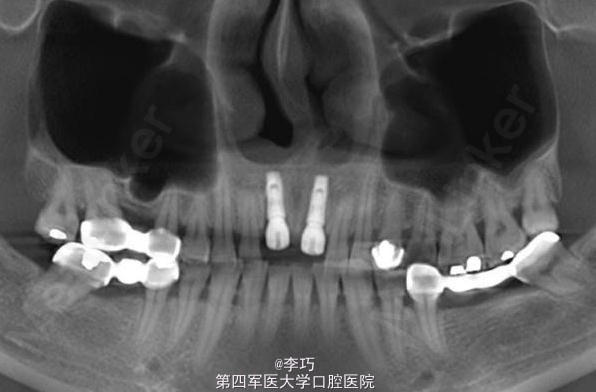

行曲面断层片和CBCT模拟植入